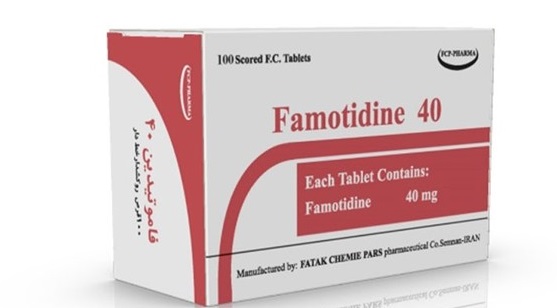

قرص فاموتیدین، بیماری ریفلاکس معده به مری (GERD) و سایر شرایطی که در آن اسید…